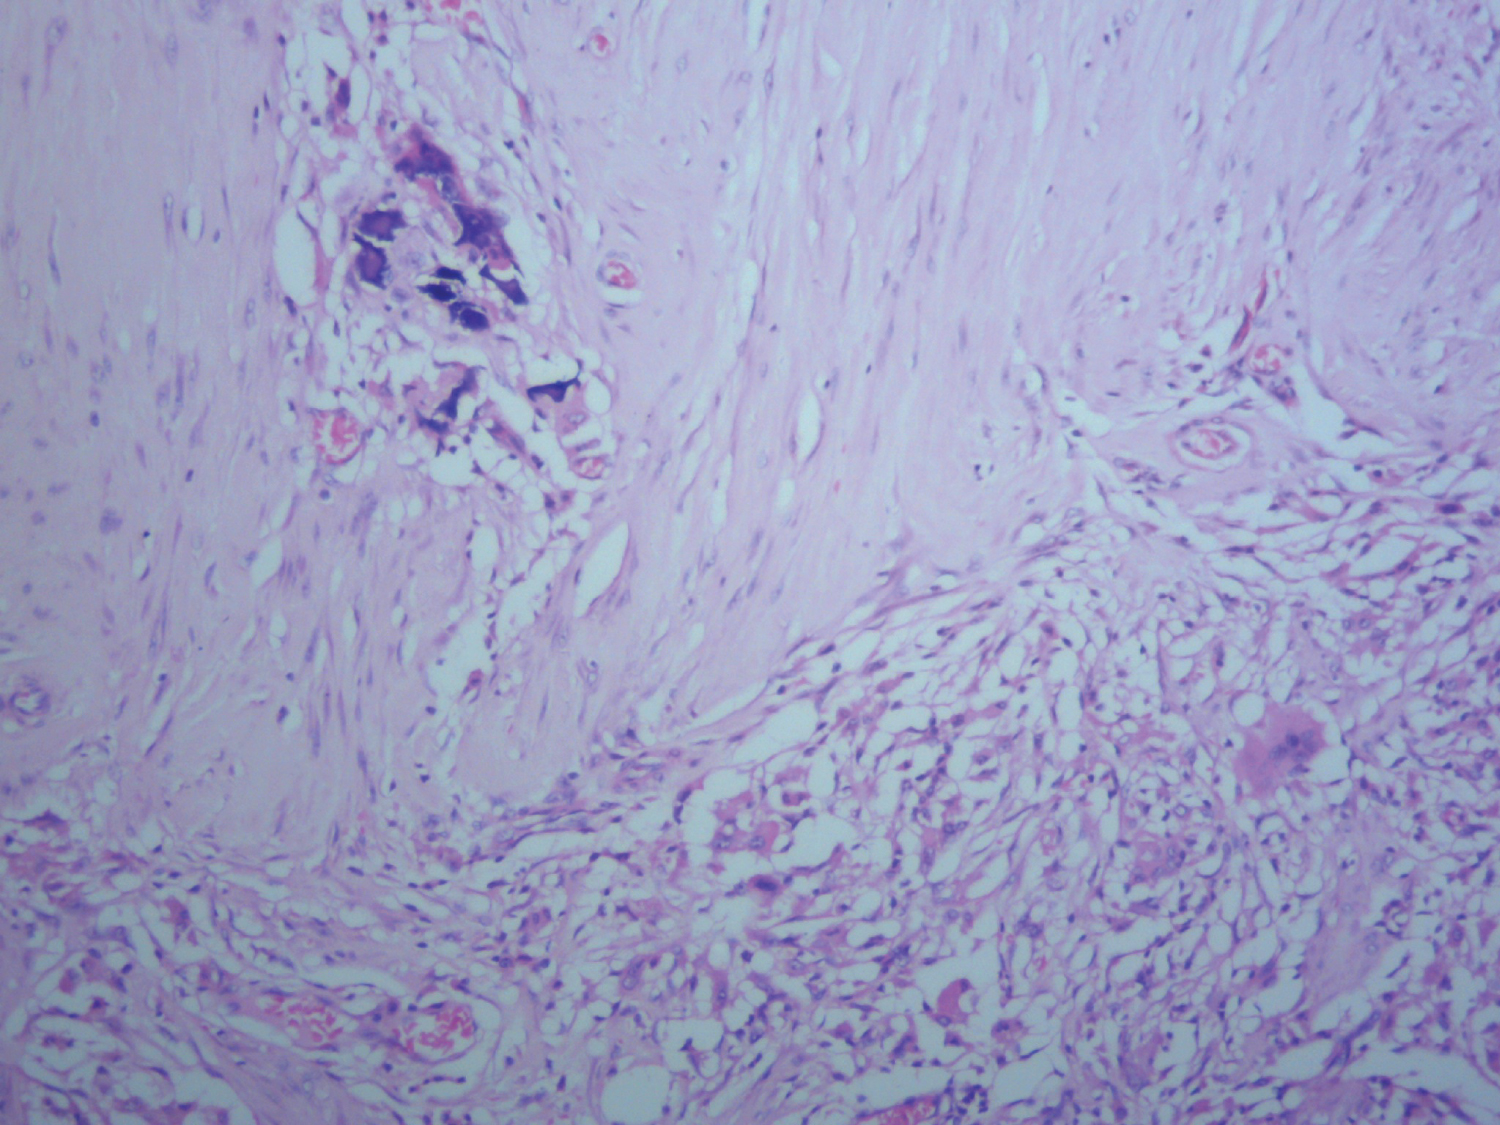

Microscopically, histologic sections of the tumour show infiltration by malignant squamous epithelial cells that are disposed in cell nests. The cells are large and pleomorphic with glassy appearance. They have vesicular nuclei and scanty cytoplasm. They show individual cell keratinization and intercellular bridges with areas of intratumoural infiltration by mononuclear inflammatory cells, comprising lymphocytes and plasma cells. Keratin pearls and areas of dystrophic calcification are seen. No ductal or glandular element is seen. The overlying skin is unremarkable (Figure 1, Figure 2 and Figure 3). The overall features are in keeping with pure squamous cell carcinoma of the breast (large cell keratinizing variant). The resection margins and the axillary lymph nodes are free of the malignant cells. Immunohistochemical staining of the tumour cells are negative for ER, PR and HER2/neu but are strongly positive for CK5/6 (Figure 4, Figure 5, Figure 6 and Figure 7).

Figure 1: Tumour cells stained with Haematoxylin and Eosin (H&E). View Figure 1

Figure 2: Focus showing area of dystrophic calcification with H&E stain. View Figure 2

Figure 3: Histological section showing intact skin on H&E stain. View Figure 3